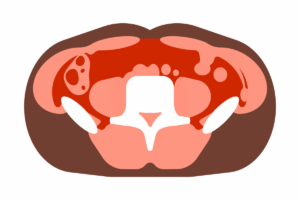

Radiological and histological examinations showed that there was severe vertebral bone damage. Micro-computed tomography revealed a large number of structural lesions in the vertebrae, especially around the lumbar and thoracic regions of the spine. There were vertebrae with little holes, as well as those with general structural disintegration. Additional tissue examination showed significant bone loss within the vertebral bodies. Marrow adiposity and degeneration of intervertebral discs were also observed in the damaged bones. Although these bones had abnormalities, the other major organs, like the liver, heart, kidney, and pituitary, were normal, implying that the abnormality was more localized in the maintenance processes of bones. The researchers studied embryonic tissues in order to identify the time when the problem developed. Although CL-11 and complement protein expression were common in embryonic bone formation, the embryos that were free of CL-11 and C3 were found to be normal skeletally at birth. This suggests that the defects are later on because of issues with bone remodeling as opposed to early development.